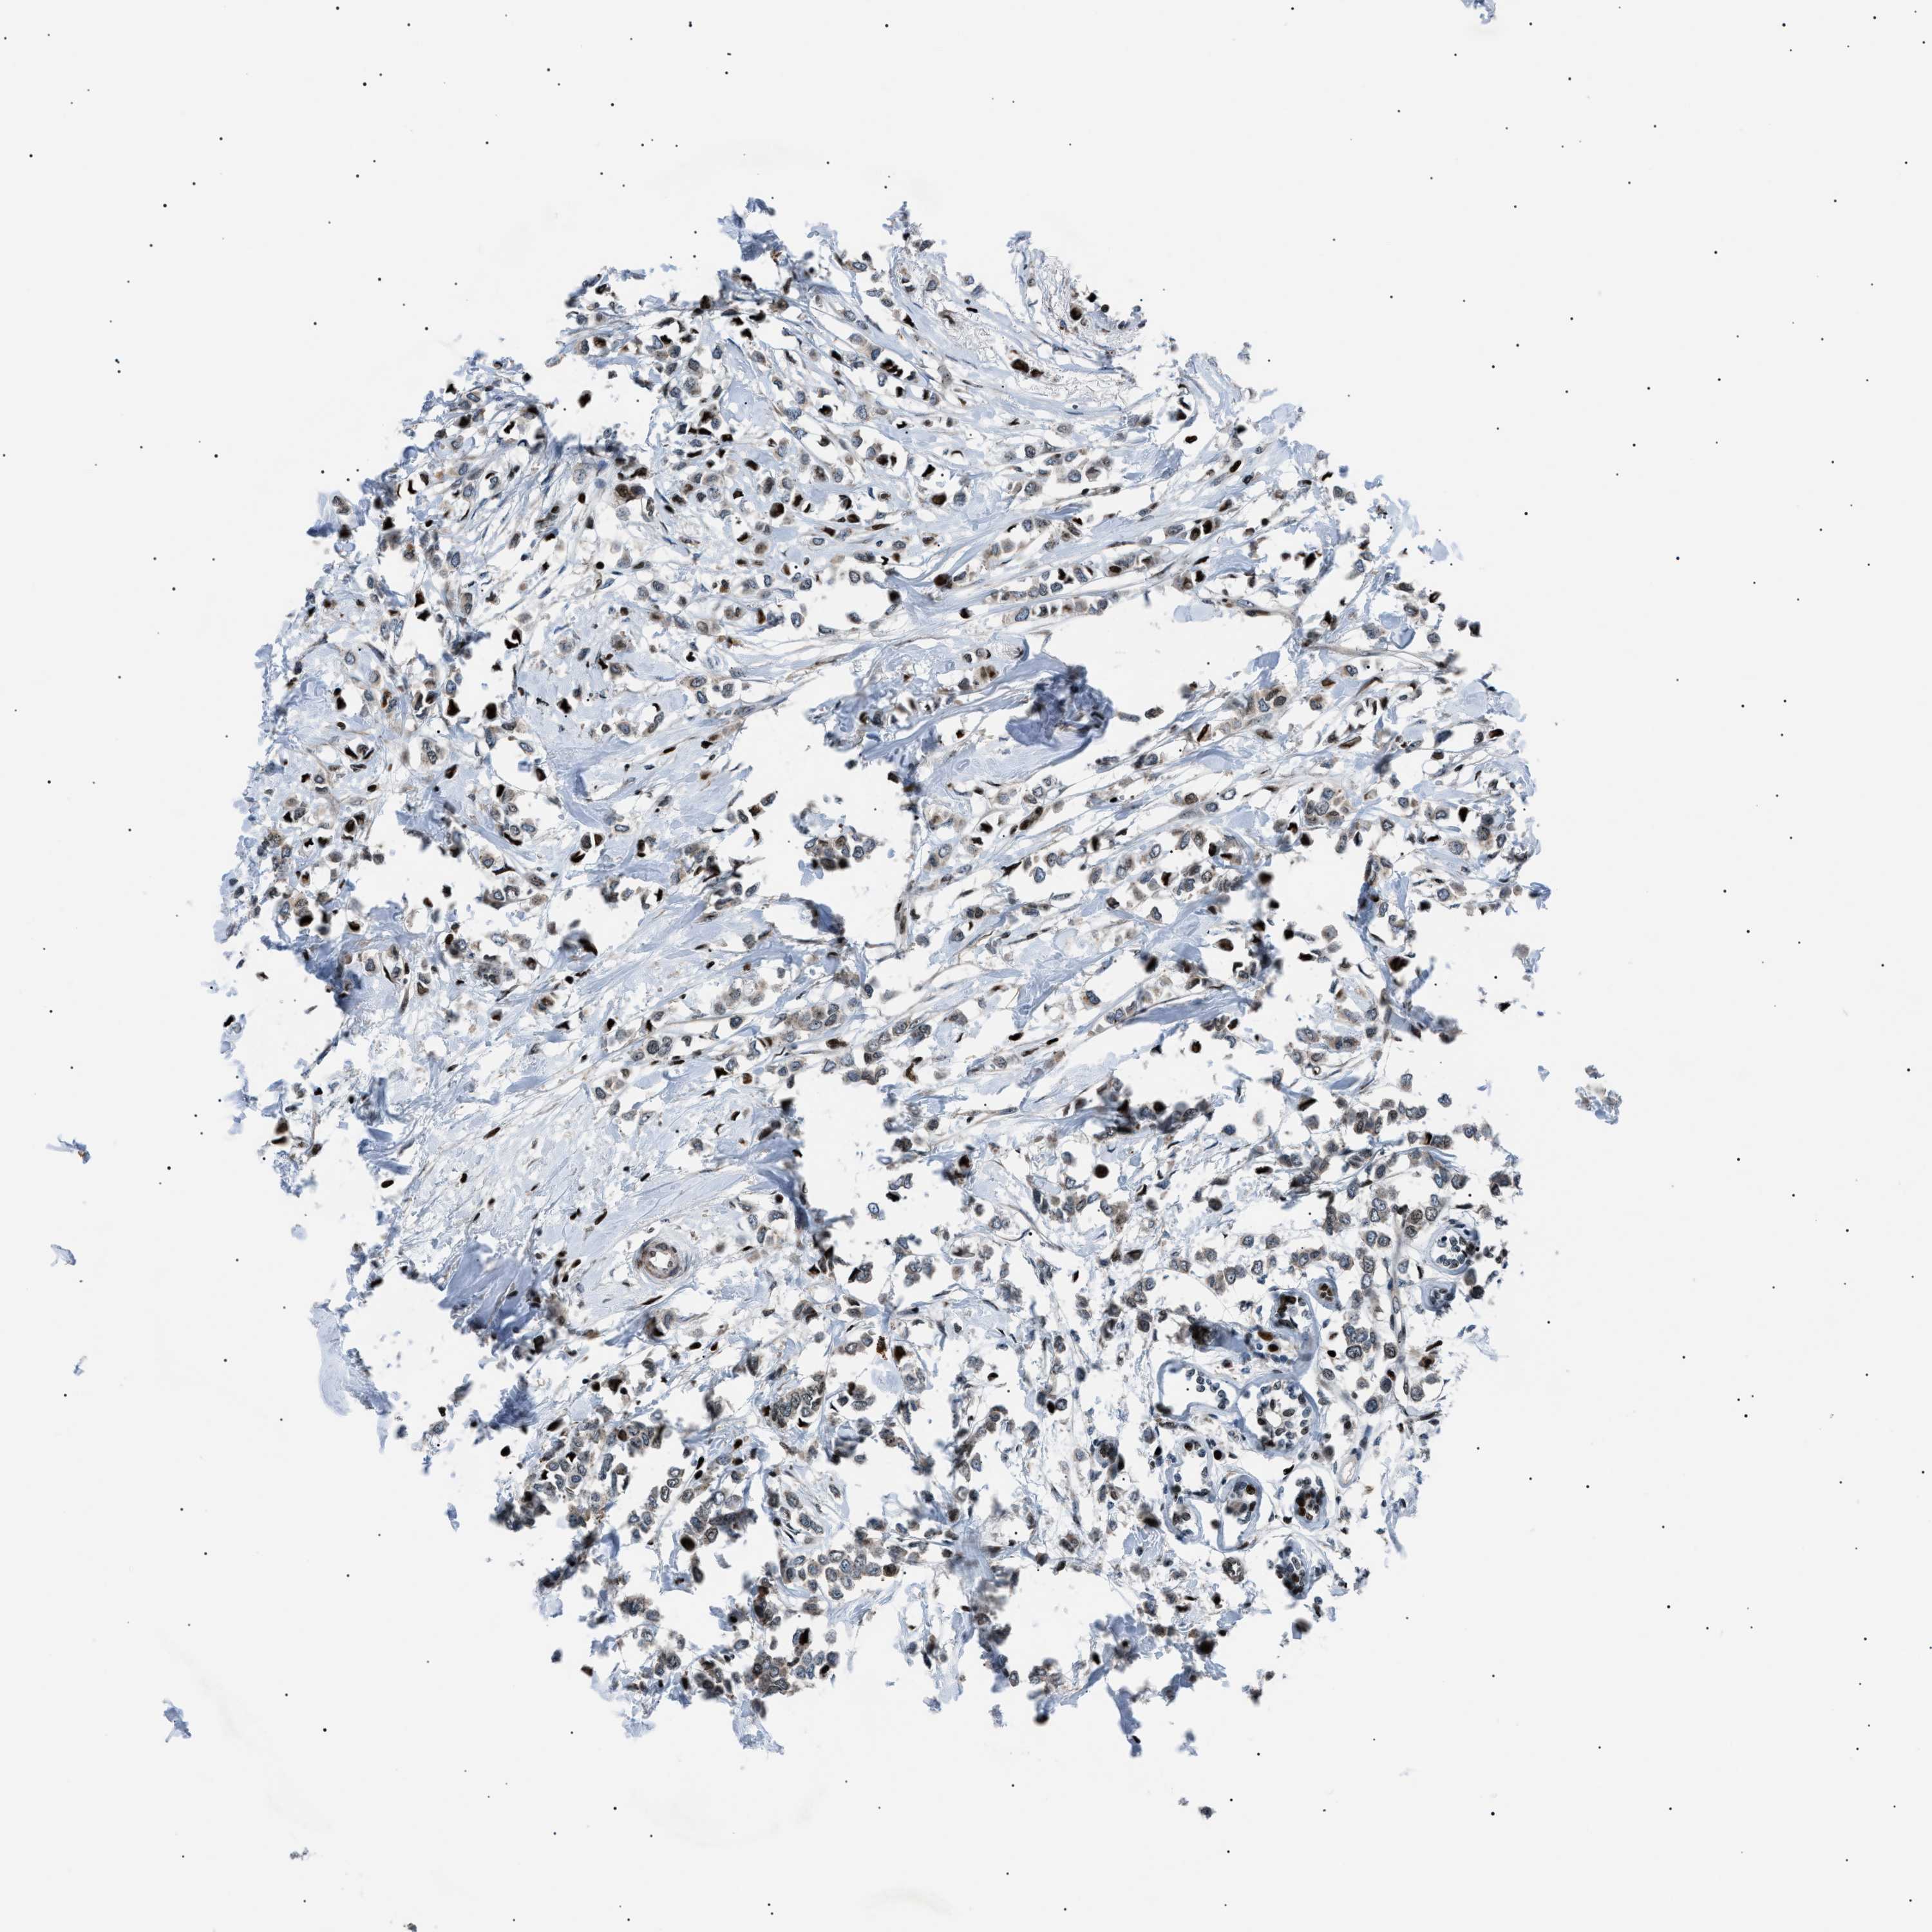

CANCER BREAST CANCER Show tissue menu

BRCA TCGA BRCA VALIDATION PROTEIN EXPRESSION

ANTIBODIES

AND

VALIDATION